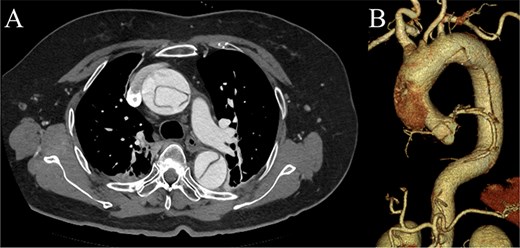

Contrast-enhanced CT image acquired on postoperative Day 2, showing the reverse rim sign.

A 70-year-old woman presented to the emergency department with sudden-onset chest and back pain. Contrast-enhanced CT revealed an ATAAD extending from the ascending aorta to the bilateral common iliac arteries. The primary entry tear extended from the ascending aorta into the aortic arch, and the false lumen remained patent throughout its entire peripheral extent (Fig. 1). Both renal arteries originated from the true lumen, and there was no malperfusion. Vital signs were stable, and the patient was not in shock. The patient underwent emergency total arch replacement with FET implantation using a 27 × 90 mm FROZENIX four-branched graft (Japan Lifeline Co., Ltd, Tokyo, Japan). The procedure was completed in 7 h and 6 min without intraoperative complications. Postoperatively, urine output declined markedly. Serum creatinine increased from a baseline of 0.81 to 2.61 mg/dl on postoperative Day 1. Diuretics failed to improve urine output, and renal replacement therapy was initiated. Contrast-enhanced CT on postoperative Day 2 showed no signs of renal malperfusion. Although the renal medulla exhibited normal enhancement, a diffuse non-enhancing area throughout the renal cortex—referred to as the “reverse rim sign”—was observed, consistent with RCN (Fig. 2). Thrombosis of the false lumen in the descending thoracic and thoracoabdominal aorta had progressed (Fig. 3). The patient developed persistent coagulopathy, with sustained hypofibrinogenemia and thrombocytopenia. On postoperative Day 2, the platelet count was 4.1 × 104/μl, D-dimer 13.5 μg/ml, and PT-INR 1.54, yielding an International Society on Thrombosis and Hemostasis DIC score of 6, consistent with overt DIC. Anticoagulation therapy with heparin and warfarin was administered. Ultimately, by postoperative Day 50, a total of 36 units of fresh frozen plasma and 100 units of platelets had been transfused; however, coagulation parameters gradually normalized thereafter, and no further transfusions were required (Fig. 4). A follow-up CT on postoperative Day 21 demonstrated further remodeling of the thrombosed false lumen. Brain magnetic resonance imaging performed on postoperative Day 9 to investigate delayed emergence revealed multiple scattered small acute ischemic infarctions involving the cerebellum, brainstem, and cerebral cortex (Fig. 5). These were not attributed to large-vessel occlusion but rather to systemic microthrombotic emboli. Despite supportive care, renal function did not recover, and maintenance dialysis was initiated. The patient was transferred to another hospital on postoperative Day 182.

DIC is frequently associated with acute kidney injury. Among them, RCN represents the most severe form, frequently resulting in irreversible renal failure. RCN is characterized by widespread coagulative necrosis due to decreased cortical perfusion. The renal cortex is more vulnerable to ischemia than the medulla because of its limited collateral circulation [4]. The “reverse rim sign,” defined by preserved medullary enhancement with cortical non-enhancement on contrast-enhanced CT, is a hallmark and highly specific imaging finding for RCN [5]. In DIC-associated RCN, systemic microthrombosis and regional hypoperfusion often cause irreversible cortical necrosis, leading to the need for long-term dialysis or kidney transplantation. In this case, RCN developed despite the absence of prolonged hypotension or renal artery malperfusion, suggesting a strong association with DIC. Diffuse RCN, as seen in the present case, is associated with worse renal outcomes than patchy RCN [6]. The advantage of diagnosing RCN, as opposed to typical acute kidney injury, is the ability to predict poor renal prognosis early on, allowing for earlier preparation for maintenance dialysis.